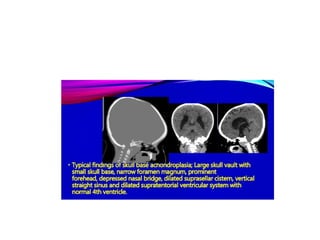

Head CT Scan → neuroanatomic

abnormalities consistent with arrested

hydrocephalus, enlarged cranial ventricles,

changes in the corpus callosum are seen.

Radiology Examination Head CTScan → neuroanatomic abnormalities consistent with arrested hydrocephalus, enlarged cranial ventricles, changes in the corpus callosum are seen. MRI → narrowing of the foramen magnum and lumbar canal stenosis